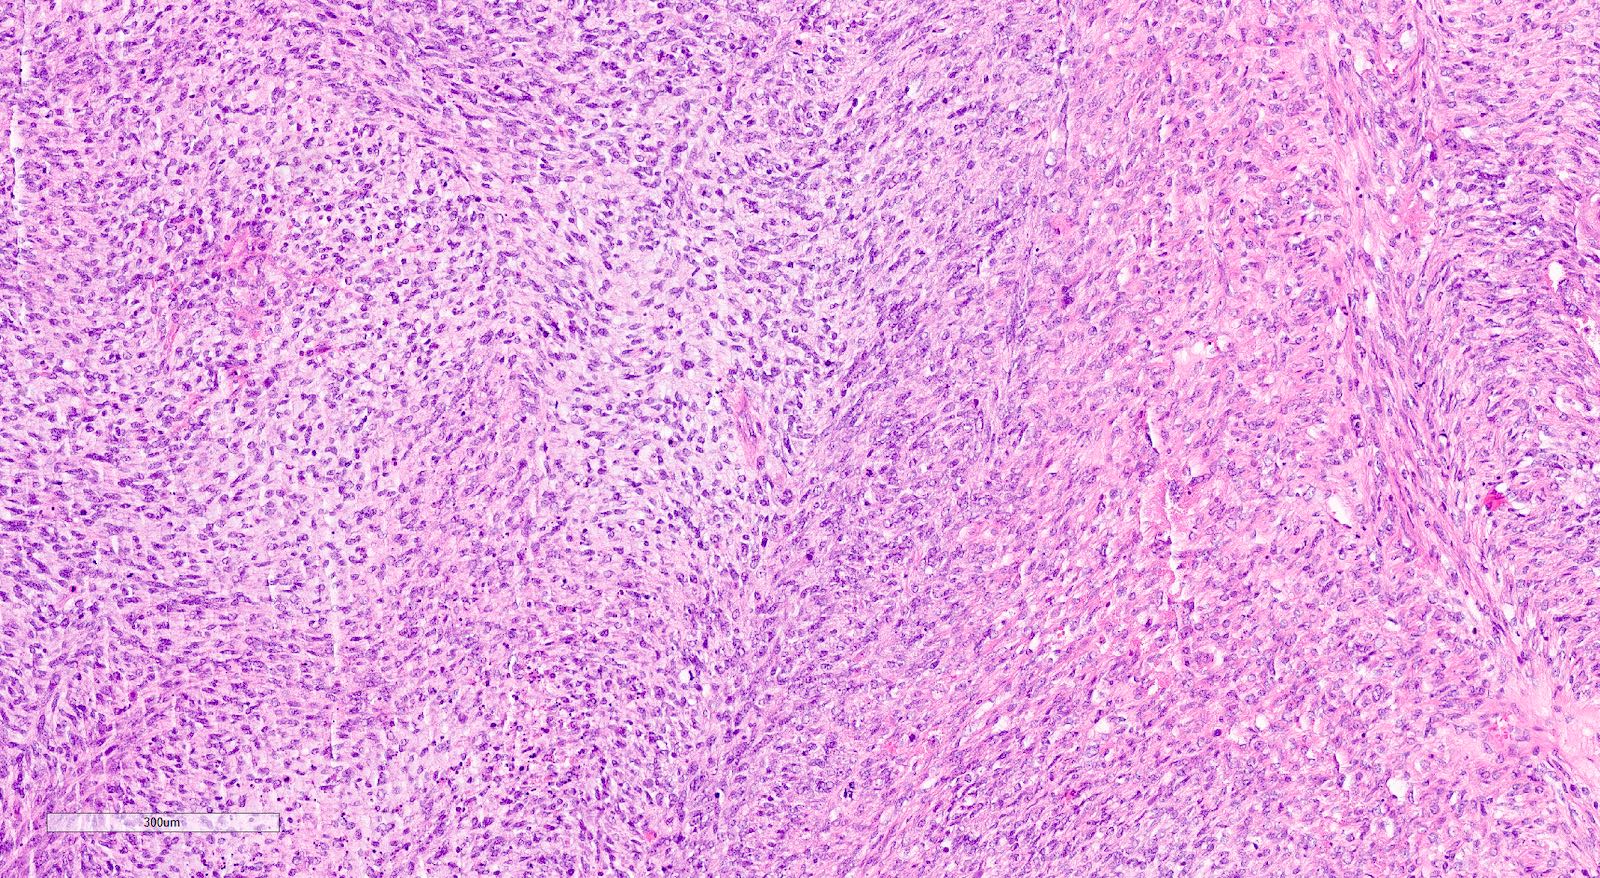

- Sarcomatous elements:

- Often spindle and pleomorphic

- 50% contain heterologous elements (most commonly rhabdomyosarcoma and chondrosarcoma) (Am J Surg Pathol 2007;31:1653)

Microscopic (histologic) images